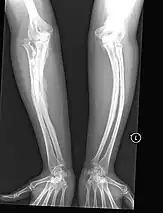

Diagnosis is typically based on medical imaging, including plain X-rays, and symptoms. In severe OI, signs on medical imaging include abnormalities in all extremities and in the spine.[97] As X-rays are often insensitive to the comparatively smaller bone density loss associated with type I OI, DEXA scans may be needed.[5]: 1514

An OI diagnosis can be confirmed through DNA or collagen protein analysis, but in many cases, the occurrence of bone fractures with little trauma and the presence of other clinical features such as blue sclerae are sufficient for a diagnosis. A skin biopsy can be performed to determine the structure and quantity of type I collagen. While DNA testing can confirm the diagnosis, it cannot absolutely exclude it because not all mutations causing OI are yet known and/or tested for.[83]: 491–492 OI type II is often diagnosed by ultrasound during pregnancy, where already multiple fractures and other characteristic features may be visible. Relative to control, OI cortical bone shows increased porosity, canal diameter, and connectivity in micro-computed tomography.[98] OI can also be detected before birth by using an in vitro genetic testing technique such as amniocentresis.[99]